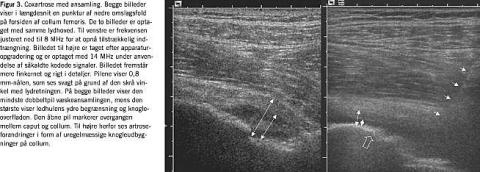

Synovialis' forhold omkring de fleste perifere og overfladenære led kan vurderes med ultralyd. Ved artrit og i mange tilfælde af artrose ses en tydelig hypertrofi af synovialis. De enkelte led har karakteristiske områder med en sådan hævelse af synovialis. Således vil synovialis over finger- eller tåled pose ud i omgivelserne over strækflader, formodentlig afhængig af mulighederne for udvidelse (Fig. 2 ). Ud over selve den hypertrofiske synovialis kan væskeansamlinger i mange tilfælde identificeres som ekkotomme strøg (Figur 2). Ganske svarende til den kliniske erfaring ses væskedannelsen mest udtalt i knæled, hvor fordelingen af ansamling i den suprapatellare reces og over ledlinjer kan afklares med UL-skanning. I hofteregionen kan man ved UL-skanning afsløre en fortykket synovialis, mens tilstedeværelsen af eventuel væskeansamling ofte først vil kunne afgøres i forbindelse med selve punkturen (Fig. 3 ). I disse led kan UL-vejledt aspiratio n give materiale til bakteriologisk differentialdiagnostik.

UL-undersøgelse af knogleoverflader er kun mulig på »fritliggende« partier af knoglen, der muliggør lydbølgernes vandring dertil. De erosive knogleforandringer, der kan ses på UL-billeder, er tydelige på tilgængelige knogleoverflader, hvor de påvises med stor sensitivitet og formentlig oftest, inden forandringerne kan ses på røntgenbilleder [23]. Uregelmæssige ledflader og randudbygninger i store led (knæ og hofte) kan således afbildes i et vist omfang (Figur 3), og erosioner i fingerled påvises (Fig. 5 ). I Tabel 1 vises et resume af indikationerne for UL-undersøgelse af de enkelte led.